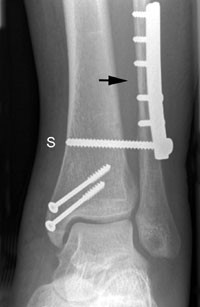

Syndesmoseskruer (fig 1) (2) ble alltid fjernet, og da 3 – 12 uker etter primæroperasjonen, med en median på åtte uker.

Det er verdt å merke seg at alle syndesmoseskruer i ankelen blir fjernet. Funksjonstiden varierer, og er angitt helt ned til tre uker. Syndesmoseskruer bør sitte inne minst åtte uker. Spesielle tilfeller som C-frakturer (fibulafraktur over ankelnivå) med ren ligamentær skade av syndesmose og mediale strukturer krever lengre funksjonstid og avlastning helst i 12 uker (5, 6). Øvrige frakturimplantater blir i de fleste tilfeller hos voksne fjernet kun ved plager, men aldersgrensen varierer betydelig. Funksjonstiden før eventuell fjerning varierer lite, men margnagler antas å gi noe raskere tilheling, og kan derfor fjernes tidligere enn plater.